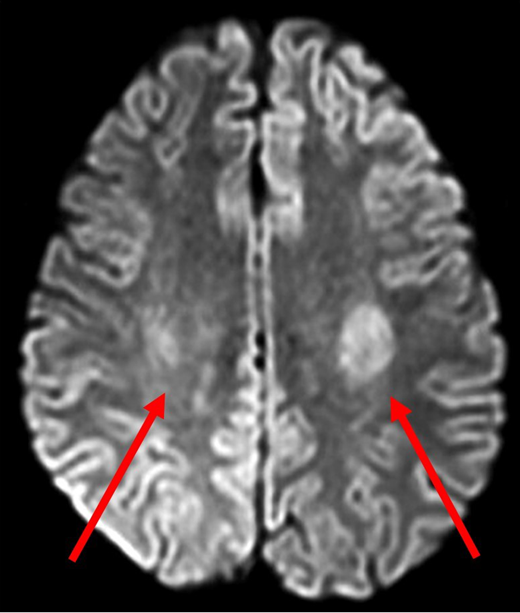

A 14-year-old Hispanic girl with high-risk B-ALL without CNS involvement was receiving standard-of-care chemotherapy according to the Children's Oncology Group protocol AALL0232. She had tolerated chemotherapy relatively well, including 6 doses of intrathecal methotrexate in the induction and consolidation phases. The first interim maintenance phase was initiated with 15 mg of intrathecal methotrexate followed by 5 g/m2 of intravenous methotrexate over 24 hours. Methotrexate cleared appropriately, and she received 3 doses of leucovorin 15 mg/m2 at hours 42, 48, and 54. Nine days later, she presented to the emergency department with acute-onset right-sided leg weakness, which progressed to the right arm and face over a 2-hour period. In addition to right paraparesis and facial droop, she was noted to have aphasia and dysarthria. Magnetic resonance imaging (MRI) performed 4 hours after the onset of symptoms showed restricted diffusion bilaterally in the centrum semiovale, greater on the left side (Figure 1). She was admitted to the intensive care unit for close observation. During the next 24 hours, her speech worsened, and she became more confused. There was moderate improvement in right-sided weakness, but she developed weakness in the left arm and leg. With continued supportive care, beginning day 3 of hospitalization, her symptoms gradually improved, facial asymmetry resolved, her speech became clearer, and she was able to swallow. She required physical therapy for 2 more days to regain her baseline strength and ambulate independently.

Diffusion-weighted MRI of patient 1 four hours after onset of symptoms. DWI demonstrated abnormal diffusion in bilateral centrum semiovale (red arrows), greater on the left side. These findings indicate increased diffusion of water in the affected regions suggestive of cytotoxic edema.